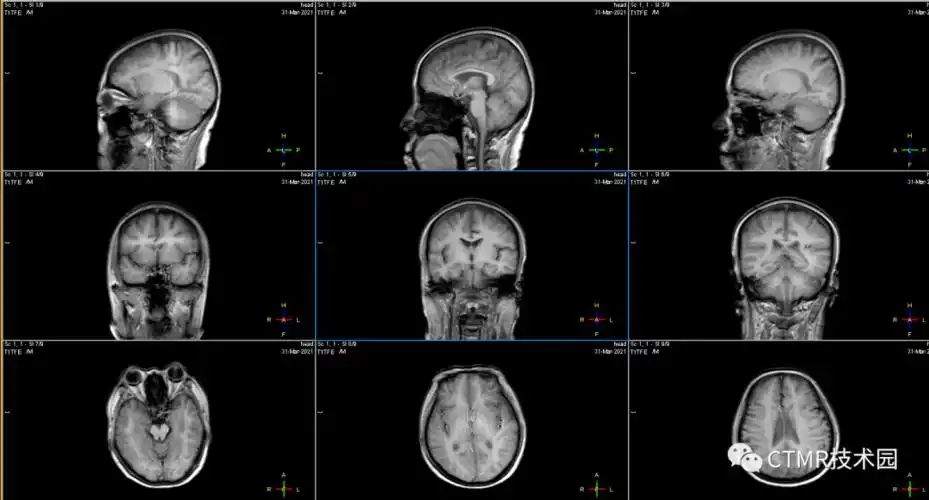

手把手教你基础颅脑mr平扫及后处理